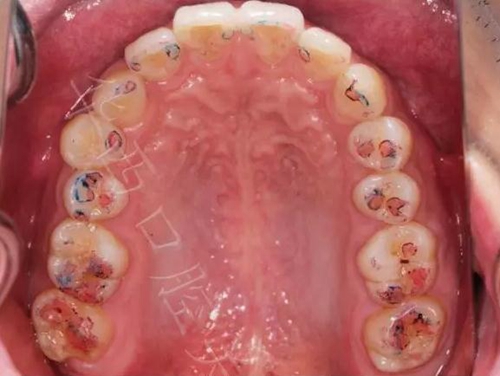

▲圖8:40µm 正中咬合

③ 結果:

▲圖9:最終結果